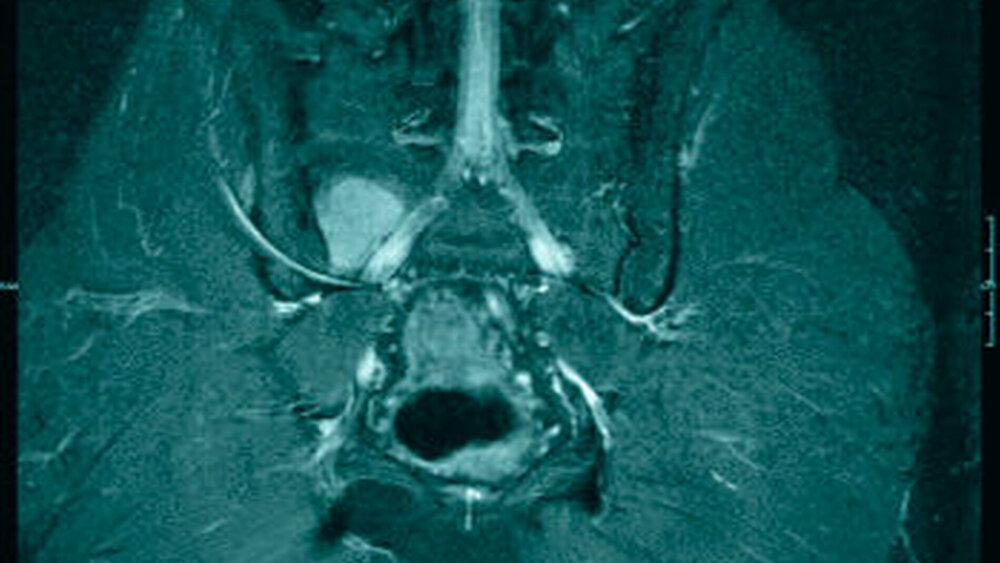

In der Computertomografie des Thorax, des Oberbauches und des Beckens mit Kontrastmittel waren unter Berücksichtigung des Skelettszintigramms multiple sklerosierte ossäre Läsionen im Sinne osteoblastischer Metastasen darstellbar. Eine in Ergänzung angefertigte Magnetresonanztomografie der kompletten Wirbelsäule inklusive der Iliosakralgelenke (Abbildung 4) zeigte multiple, bis zu 1,9 cm große Metastasen im Skelettsystem.